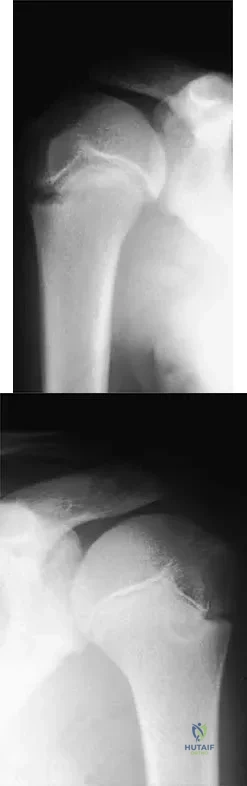

Question 76

A 15-year-old baseball pitcher who reports increasing pain in his right shoulder over the past 3 weeks states that the pain increases the more he pitches. Radiographs of both shoulders are shown in Figures 35a and 35b. What is the next most appropriate step in management?

Explanation